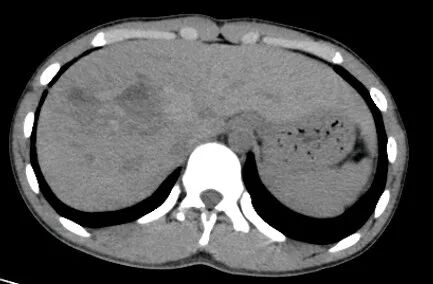

肾挫伤

肾挫伤是一种比较多见的肾损伤,肾组织损伤较轻,肾包膜和肾盂大多保持完整,肾实质内产生瘀血或血肿,并有少量血液流入肾盂导致血尿。肾挫伤在X线造影片上可不显示形态上的改变。一般均能自行愈合而不造成严重后果。